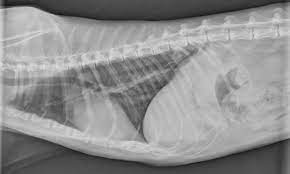

Signs Of Lung Cancer In Cats : Thoracic Tumors Lung Dr Julius Liptak - Symptoms of feline lymphoma cancer according to dr.. Other common symptoms of lymphoma in cats include swollen lymph nodes, loss of appetite, weight loss, and difficulty breathing. This can occur because of spread of tumor to the bones of the limbs (more common in cats), or due to a secondary effect that the tumor has on bone growth (more common in dogs). Arteaga, these are the symptoms of lymphoma in cats: Lymphoma and lymphosarcoma is common among cats with felv infections. Adenocarcinoma (papillary or bronchioalveolar) is the.

A severe acute attack is likely to result in a cat's death if veterinary treatment is not immediately available. That's the thing about cancer in cats. Externally we can see lumps and bumps. In fact, cancer accounts for almost half of the deaths of pets over 10 years of age. Panting, abdominal effort when breathing, wheezing, coughing, and inability to exercise are also signs of lung tumours in cats. Lymphoma and lymphosarcoma is common among cats with felv infections. These signs often include decreased appetite, weight loss, increased thirst, and vomiting. This combined with the fact that cats tend to hide illness well means that when we find cancer in cats it's often both serious and advanced. Cats with lymphoma may have an increased or decreased appetite, or you may notice no change in appetite. Radiation also works for localized tumors, particularly tissue that can't be surgically removed. This can occur because of spread of tumor to the bones of the limbs (more common in cats), or due to a secondary effect that the tumor has on bone growth (more common in dogs). Arteaga, these are the symptoms of lymphoma in cats: Occasionally dogs and cats with lung cancer are lame.

Cancers Tumors In Cats Hill S Pet from www.hillspet.com Panting, abdominal effort when breathing, wheezing, coughing, and inability to exercise are also signs of lung tumours in cats. These signs often include decreased appetite, weight loss, increased thirst, and vomiting. Respiratory, nasal or pulmonary carcinoma is most common in the muzzle and lung cancer in cats. Bad breath may indicate oral cancer, although it's also a symptom of a sinus infection. This can occur because of spread of tumor to the bones of the limbs (more common in cats), or due to a secondary effect that the tumor has on bone growth (more common in dogs). It causes difficulty breathing, snorting, sneezing, coughing and nasal secretions. Up to 25 percent of pets with lung cancer may not show any clinical signs of illness. Learn more about pneumonia in cats.

In cats with renal lymphoma, signs associated with kidney failure may be seen. Difficulty in breathing can be a sign,. This can occur because of spread of tumor to the bones of the limbs (more common in cats), or due to a secondary effect that the tumor has on bone growth (more common in dogs). Terminal respiratory secretions (saliva and bronchial secretions) can build up in the back of the cat's throat as the coughing and swallowing reflexes decline, which can cause a gurgling or rattling sound, known as the death rattle Cancer may be localized, or it may invade adjacent tissue and spread throughout the body. Although cancer may be one of the potential causes of a variety of different signs (especially in older cats), it is important to remember that many other diseases commonly cause the same signs as cancer and that, even where cancer is diagnosed, there may well be treatment options that will enable control or management of the disease, at least. Very few mammary gland growths in cats are benign—85 to 90 percent are malignant and spread to lymph nodes, lungs and the chest cavity. Lung cancer (pulmonary neoplasia) is a malignant tumour of the lungs that can be primary (originating in the lungs), or secondary (having originated elsewhere and spread to the lungs). Other symptoms of lung cancer include: Only about two thirds of dogs and cats actually exhibit clinical signs. The signs indicating a primary lung tumor can vary, depending on the location of the tumor, speed of tumor growth, and presence of previous or current lung disease. Chemotherapy is an option for the cat that has cancer in multiple areas of the body. The cat will have a dry cough and will be less active.

Cancer In Cats Elwood Vet from images.squarespace-cdn.com However, there are many different type of cancer, and cats can get other cancers, even very rare ones. For example, certain breathing problems and coughing are surprisingly uncommon; Symptoms of feline lymphoma cancer according to dr. Vomiting and diarrhea are common signs of gastrointestinal lymphoma. Less than a third of cats diagnosed with lung cancer have breathing problems. The signs indicating a primary lung tumor can vary, depending on the location of the tumor, speed of tumor growth, and presence of previous or current lung disease. If the cancer originates in other parts of the body, the coughing will not be present in the initial stages of the disease. This type of cancer is rare in cats, and accounts for less than 1% of all tumours.